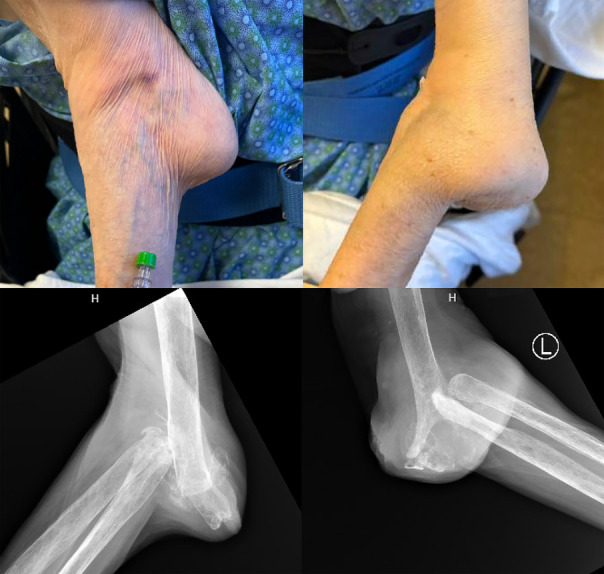

临床图片:肘关节外翻:破坏性焦磷酸钙晶体关节炎。

Clinical Images: Flail elbows: destructive calcium pyrophosphate crystal arthritis.